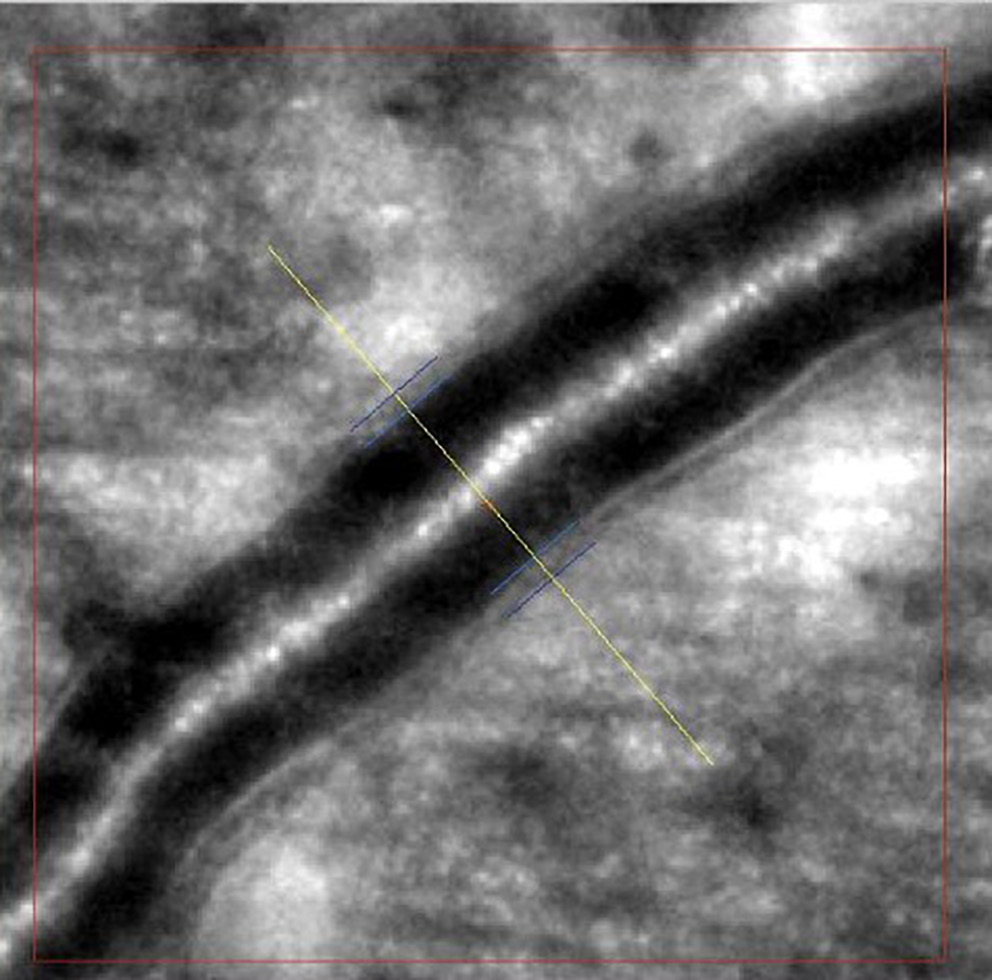

Images of retinal arterioles using an AO retinal camera (rtx1™; Imagine Eyes, Orsay, France) were captured in both patient groups. Before imaging, participants received 1 drop of 1% tropicamide for pupil dilation. Retinal artery images were analyzed with AOdetectArtery software (rtx1™; Imagine Eyes), focusing on the superior quadrant arterioles with a lumen diameter of at least 40 μm and no bifurcations. Two measurements were taken, and the highest-quality scan was selected for analysis.

The main vascular parameters obtained with AO were total vessel diameter (TD), lumen diameter (LD) and wall thickness (WT). The software also calculates 2 additional vascular metrics: The wall-to-lumen ratio (WLR), defined as wall thickness (WT) divided by lumen diameter (LD), and the wall cross-sectional area (WCSA), computed as π × [(TD/2)2 – (LD/2)2], which represents the area occupied by the vessel wall (Figure 1, Figure 2).